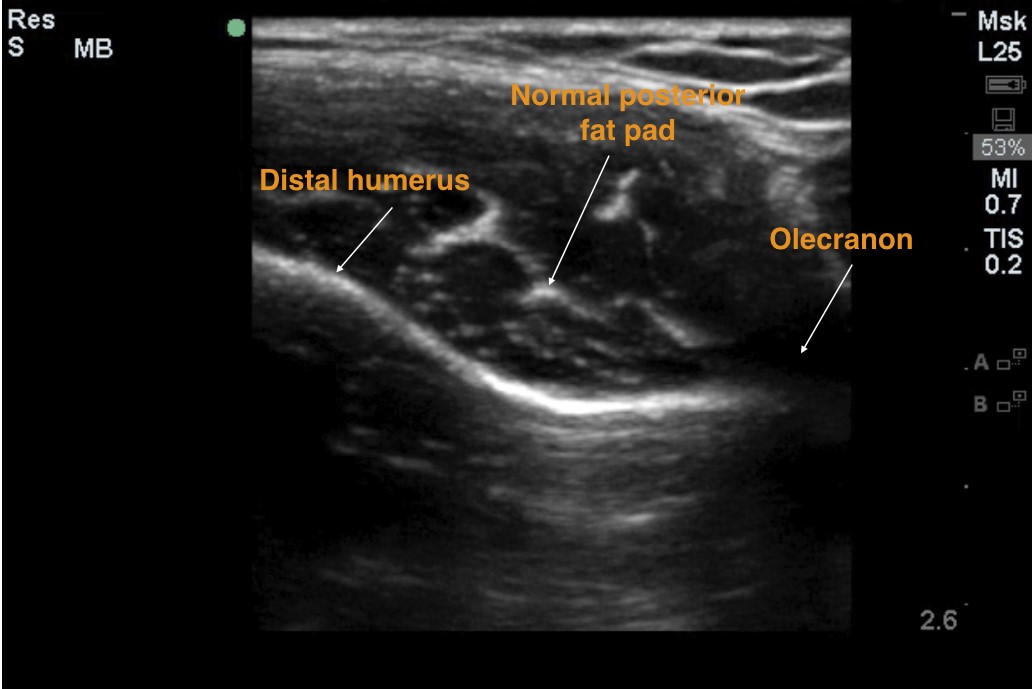

With the elbow bent at 90 degrees (Figure 1), use the linear probe in longitudinal (Figure 2) and transverse axes (Figure 3) to identify (a) distal humerus (b) olecranon (c) posterior fat pad

Figure 2: Longitudinal view of the distal humerus showing a normal posterior fat pad and the olecranon